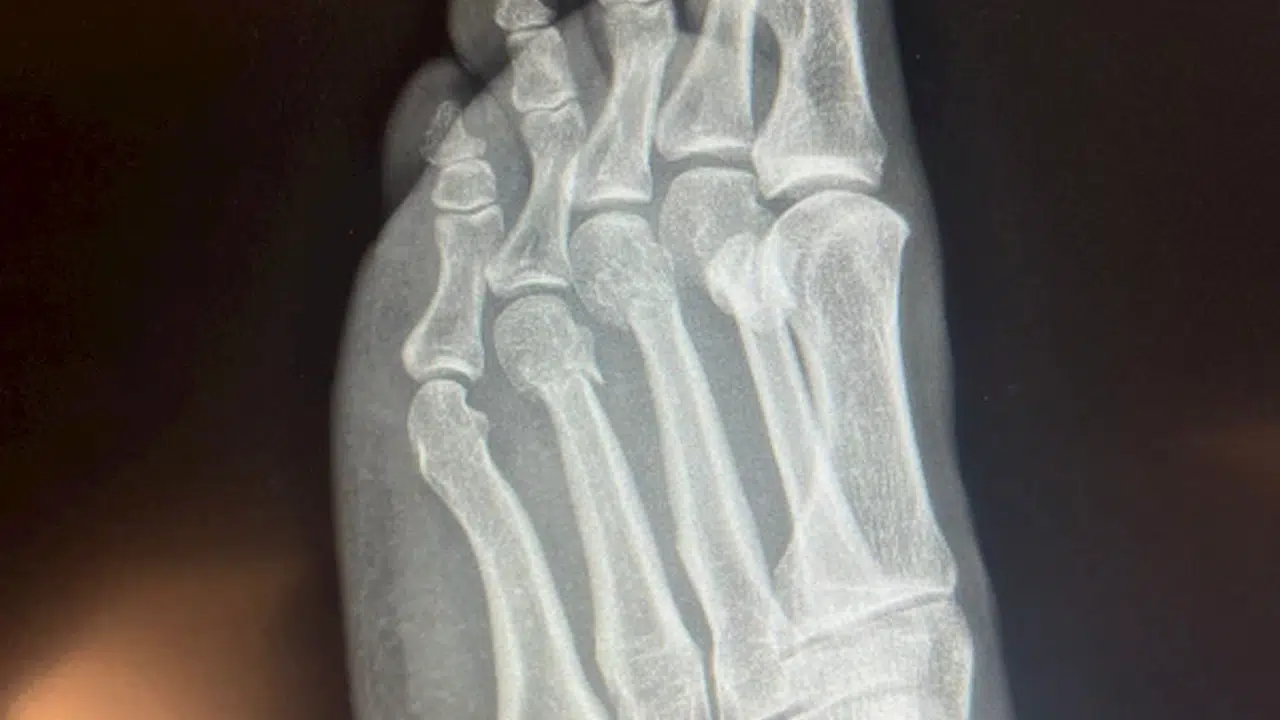

Özgür Özel'den, 'ayağından vuruldu' iddialarına röntgenli yanıt

Aliekber METE/ANKARA, (DHA)- CHP Genel Başkanı Özgür Özel, 'ayağından vuruldu' yönündeki iddialara röntgen filmlerini paylaşarak yanıt verdi.

CHP Genel Başkanı Özgür Özel'in geçen hafta evinde geçirdiği kaza sonucunda ayağında kırıklar meydana gelmişti. Kazanın duyulmasının ardından bazı sosyal medya hesaplarında, Özgür Özel'in ayağından vurulduğu iddia edildi. Tartışmaların sürmesi üzerine Özel, ayağının röntgen filmlerini paylaştı. (DHA)